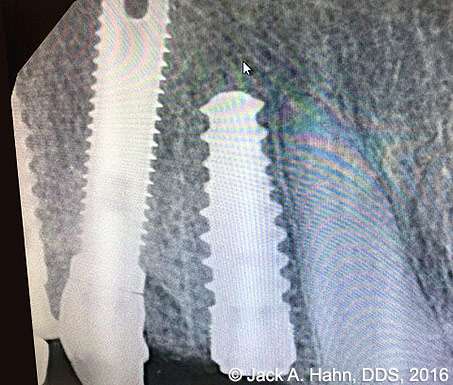

CASE #4 Trauma Case – Central Incisors Internal / External Resorption

Implants, that replace failed endo- or perio-compromised teeth, have a MUCH higher success rate with laser decontamination of the osteotomy site. LightScalpel laser surgical and perio laser tips ensure excellent access to extraction socket for the optimum removal of granulation tissue and socket decontamination (protocol involves manual curettage of the socket with alternating rinsing and lasing).

The patient, a 17-year-old female was involved in a water slide accident 3 years ago. As a result, both central incisors were avulsed and an endodontist replanted them. Both teeth exhibited internal and external resorption. Dr. Hahn extracted both central incisors, removed all the root fragments and sanitized the sites with the LightScalpel laser which also eliminated any granulation tissue. The #8 area was prepared to place a Hahn 4.3×13 Implant and #9 was prepared for a Hahn 3.5×13. 3mm tall Hahn healing abuts were placed slightly below the gingival-tissue level to help develop an emergence profile when at the restoration time in 4 months. Upon seeing the x-ray, Dr. Hahn tightened the healing abutment on #9 to be sure that it was completely seated on the implant. 45nucm. stability was achieved on both implants. He then placed some bone putty to seal any openings. To be on the safe side, he decided to place a temporary partial instead of immediate temporary prosthetics.